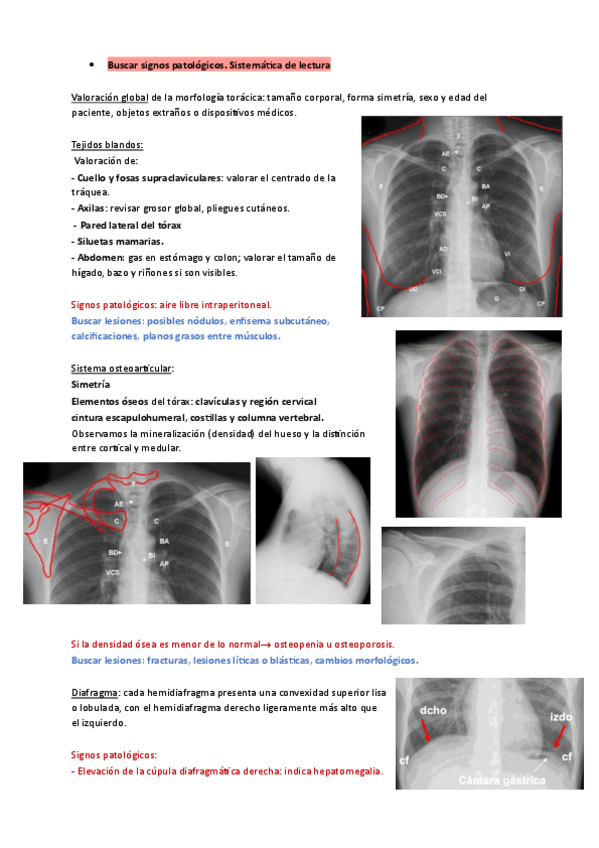

He publicado nuevos apuntes de 3º Radiología: interpretar-radiografia-de-torax.pdf

15 páginas